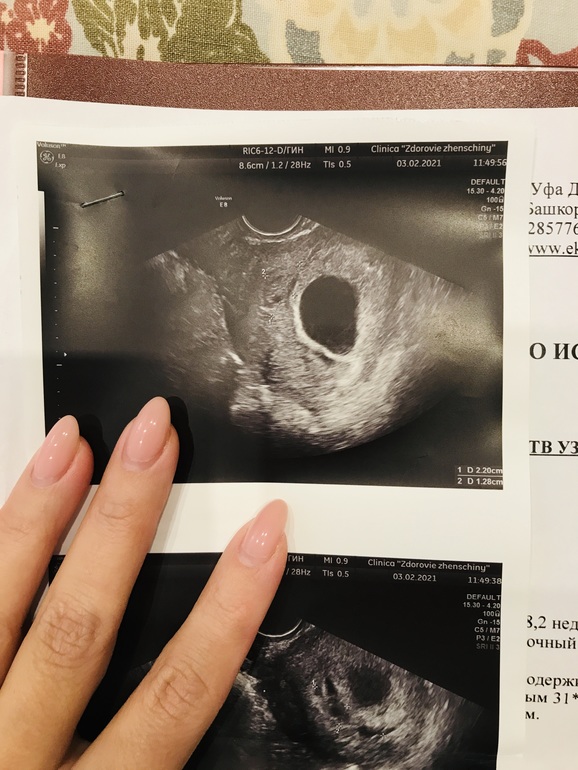

УЗИ, КТГ, доплерДевочки у кого были гематомы в 1 триместре. Подскажите или покажите как они у вас выглядят на снимке. Была я на приеме у своего врача и он говорит то что не похоже что это гематомы. Показал узисту который работает у них в клинике. Он так же сказал что это не гематомы. Сделали мне повторно узи и ничего не нашли. Даже врач мой стоял и смотрел на монитор. Ничего не беспокоит живот не болит, выделений нет...

Вот мне тоже сказали что черное должно быть. У меня вроде и черное но маленькое.. а по размерам узи должно быть большое. Не знаю даже. Надеюсь ничего нет

Алина, я не специалист, но явного "мешочка" отдельного не вижу, он должен быть с разных сторон виден, а у вас с разных ракурсов то есть "черные точки", то нет. Не переживайте, если бы была явная гематома, ее бы подтвердили бы на всех УЗИ.